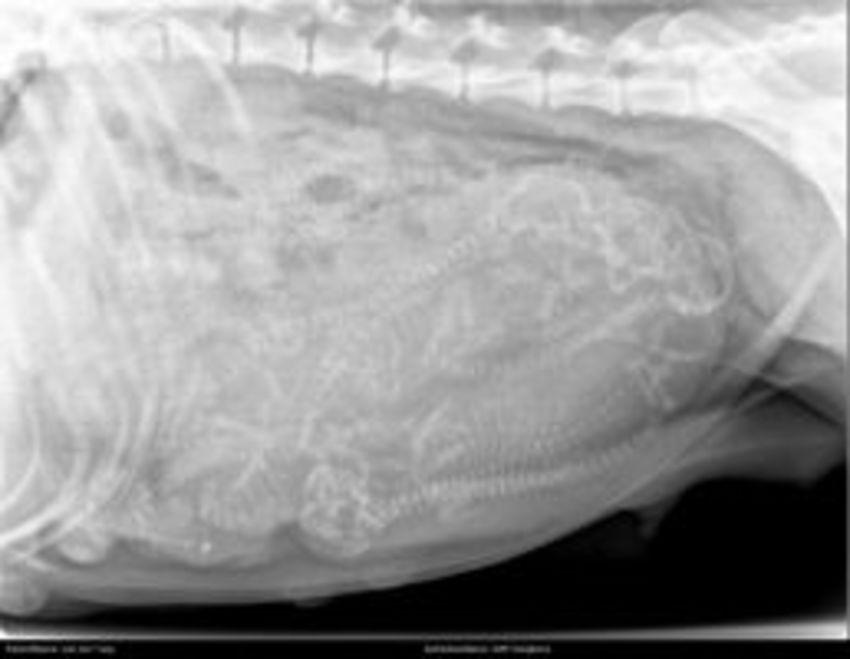

Honden foto's

• honden foto's